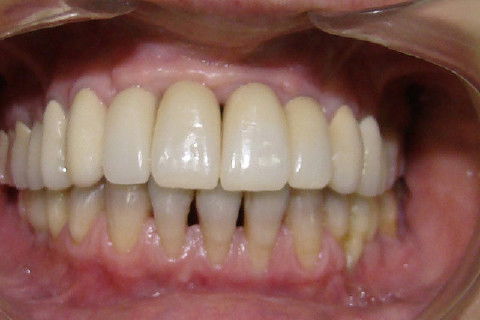

Finalização do tratamento reabilitador, com coroas metalo-ceramicas superiores e coroas unidas no lado direito da mandibula e unitaria da lado esquerdo

Sorriso final da paciente

Paciente portadora de reabilitação superior com protese fixa ferulizada e diastemas nos incisivos inferiores, procurou tratamento para "individualizar"os dentes, principalmente os superiores. No planejamento ficou estabelecido que seriam feitos enxertos de elevação do soalho do seio maxilar bilateral e enxertos em bloco na região anterior da maxila. Na mandibula tratamento ortodontico. Após o periodo de cicatrização dos enxertos, implantes foram colocados na maxila. Na mandibula após o termino do tratamento ortodontico, foram colocados implantes. Proteses temporarias foram instaladas e acompanhadas por 6 meses e então feram feitas as reabilitações proteticas superiores e inferiores.